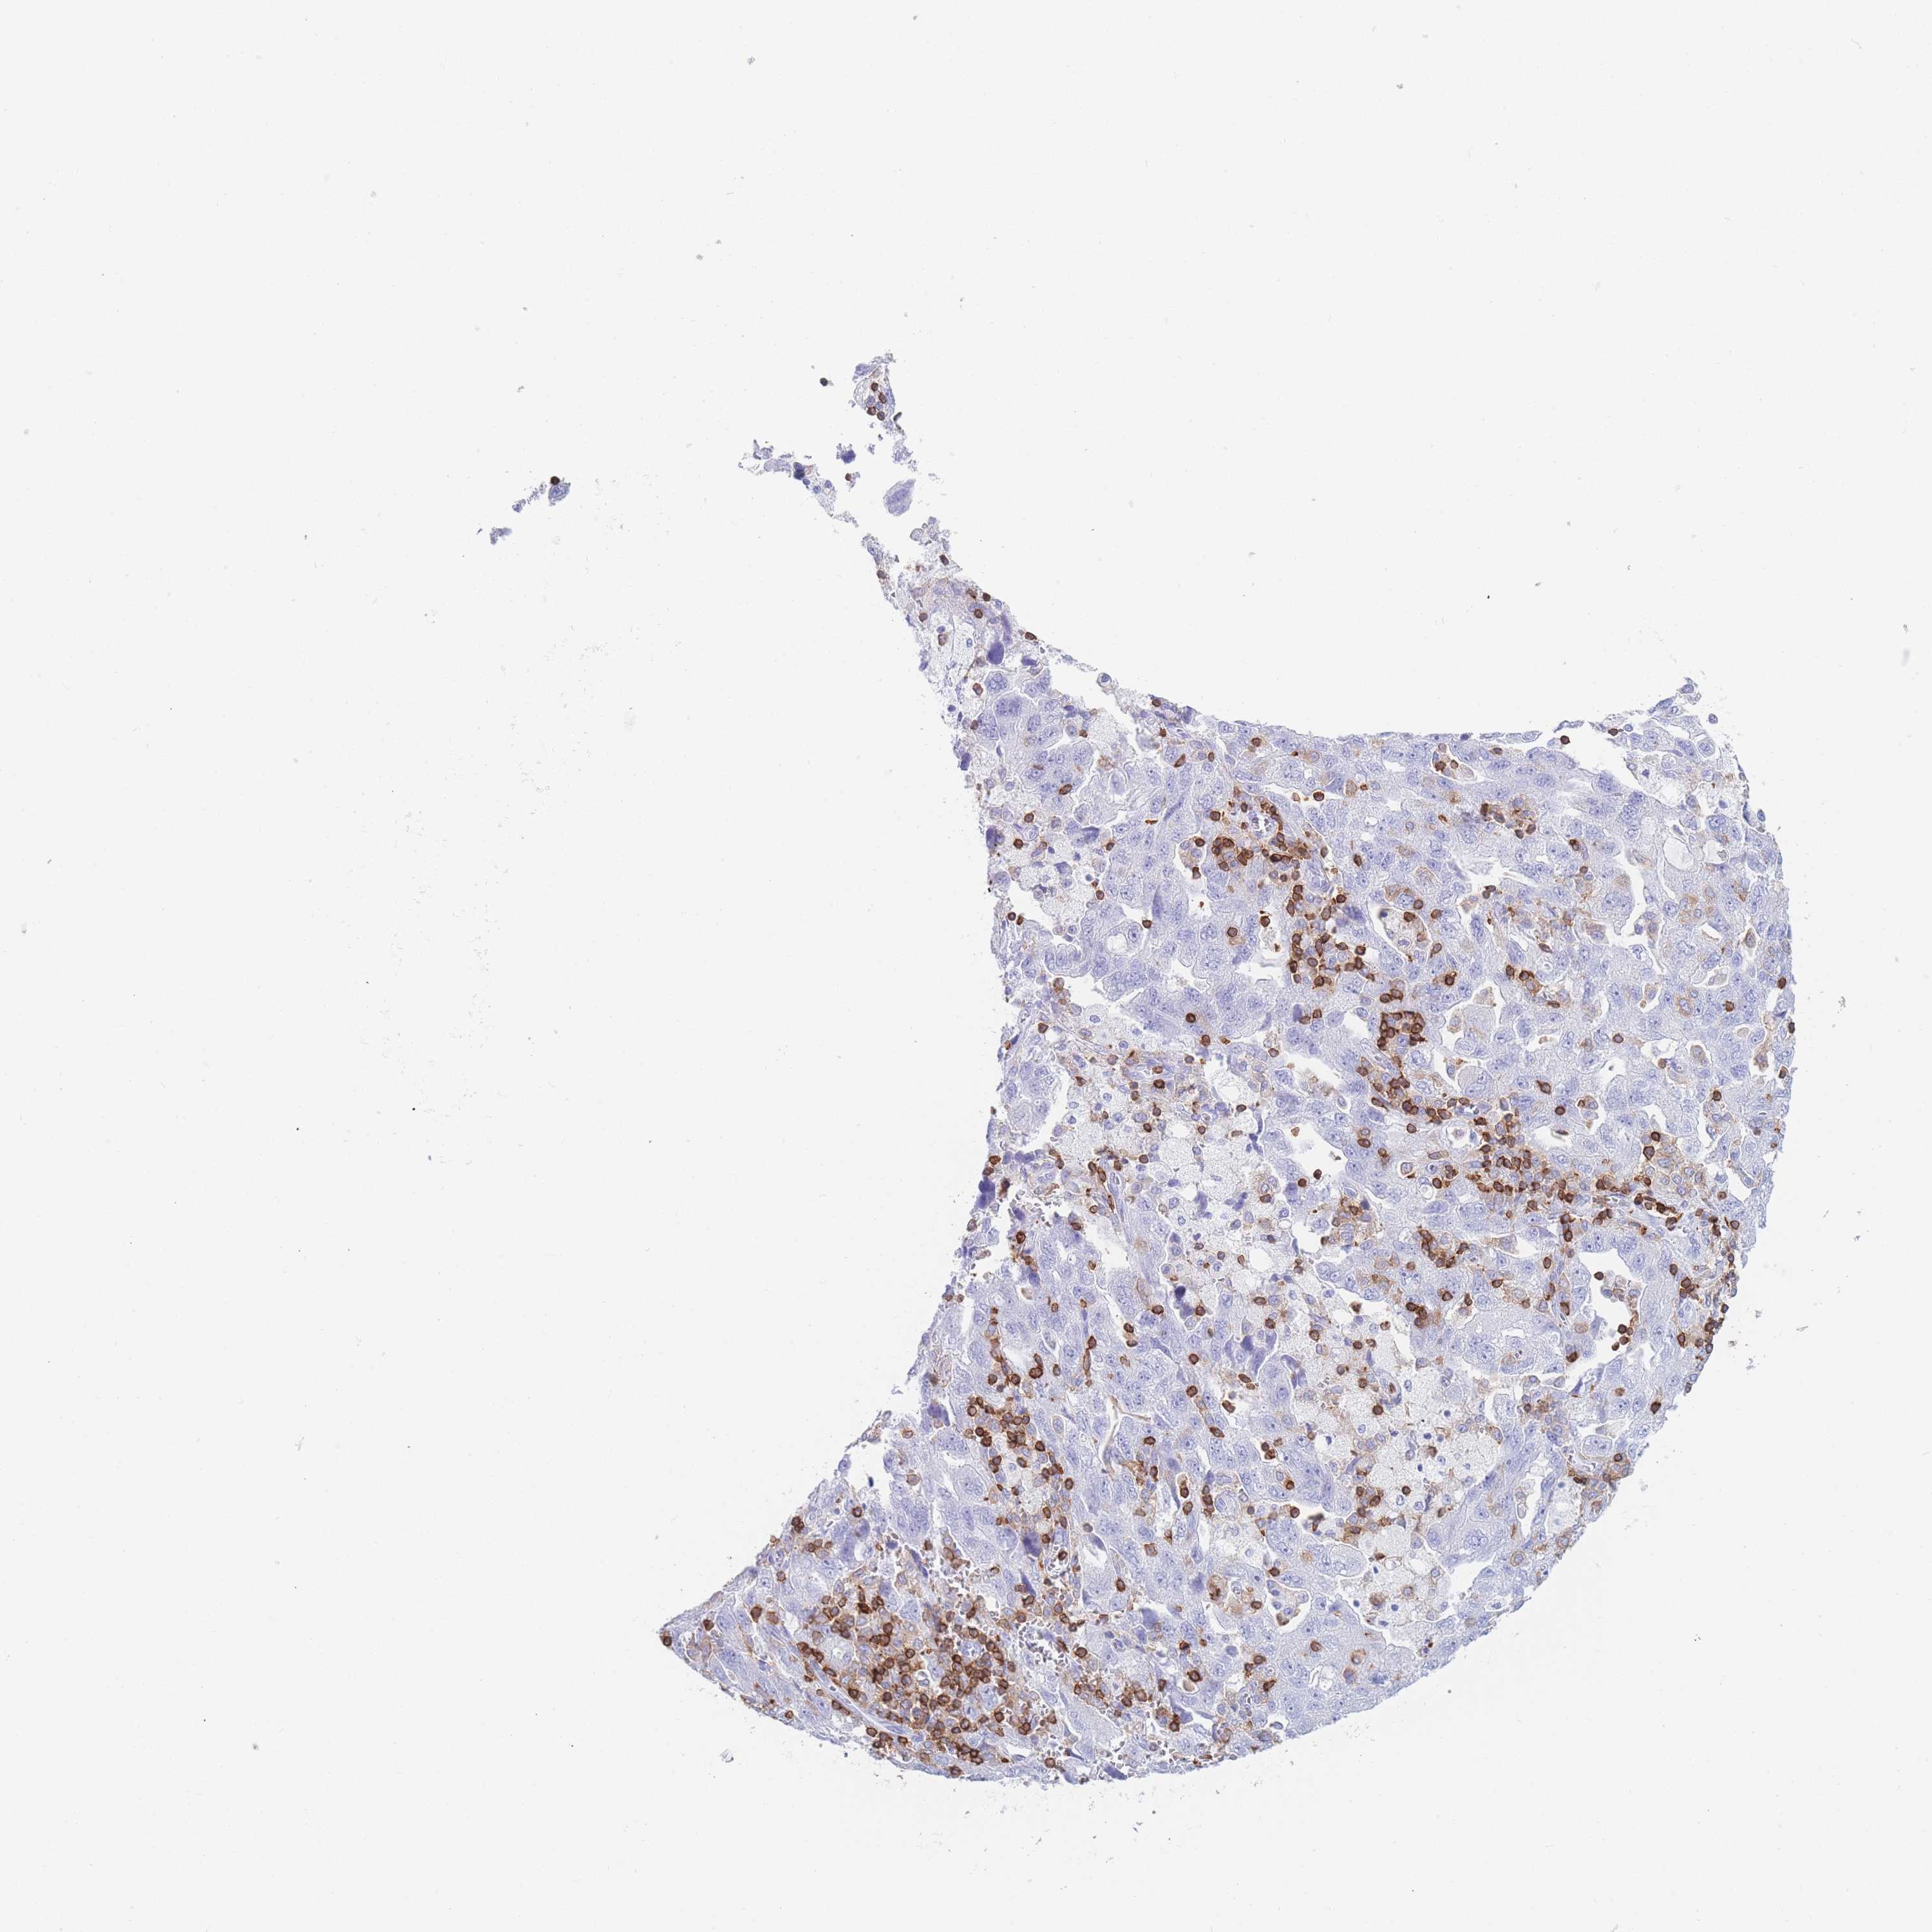

OVARIAN CANCER - Protein expressioni

A mouse-over function shows sample information and annotation data. Click on an image to view it in a full screen mode. Samples can be filtered based on level of antibody staining by selecting one or several of the following categories: high, medium, low and not detected. The assay and annotation is described here.

Note that samples used for immunohistochemistry by the Human Protein Atlas do not correspond to samples in the TCGA dataset.

Antibody stainingi

Antibody staining in the annotated cell types in the current human tissue is reported as not detected, low, medium, or high, based on conventional immunohistochemistry profiling in selected tissues. This score is based on the combination of the staining intensity and fraction of stained cells.

Each image is clickable and will lead to virtual microscopy that enables deeper exploration of all samples and also displays staining intensity scores, fraction scores and subcellular localization as well as patient and tissue information for each sample.

Antibody HPA051132

Antibody CAB046473

Staining

High

Medium

Low

Not detected

Intensity

Strong

Moderate

Weak

Negative

Quantity

>75%

75%-25%

<25%

None

Location

Nuclear

Cytoplasmic/membranous

Cytoplasmic/membranous,nuclear

Cystadenocarcinoma, serous, NOS

Carcinoma, NOS

Cystadenocarcinoma, mucinous, NOS

Carcinoma, endometroid